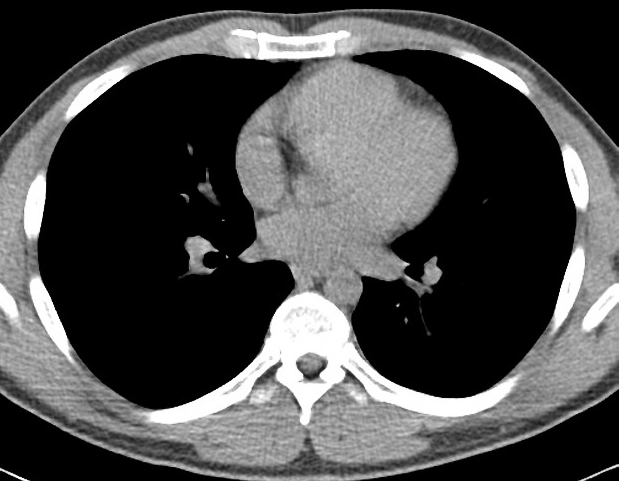

We used the Chest CT-Scan images111https://www.kaggle.com/datasets/mohamedhanyyy/chest-ctscan-images?datasetId=839140 [18] dataset for our simulations. This is one of the most commonly used datasets for CT scan images. Three distinct forms of chest cancer (adenocarcinoma, large cell carcinoma, squamous cell carcinoma), as well as normal CT-Scan images, are included in this dataset, as mentioned in Figure 2, in which the red circles indicate the affected regions. These CT scan images reveal differences in cancer types, imaging protocols, resolution, and contrast across different hospitals while still being useful to build a single, robust global model. Through these various cancer types appearing in CT scans, the visuals further highlight the problem of accurate tumor detection and classification. The features of the dataset are mentioned in the Table 1.

![]() |

| Adenocarcinoma | Large Cell Carcinoma |

| Squamous Cell Carcinoma | Normal CT-Scan |